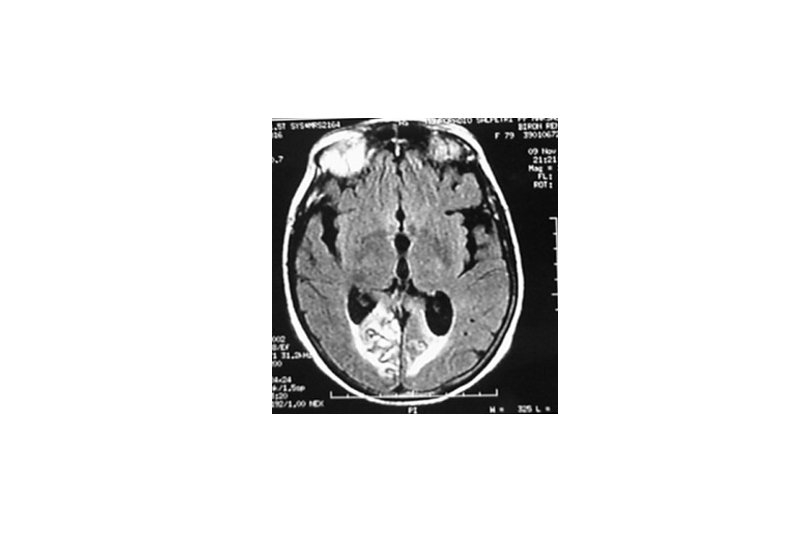

Lésion bilatérale des voies visuelles postérieures: Cécité cérébrale • Lésions bi-occipitales corticales ou sous corticales • Difficulté diagnostique Diagnostique différentiel d’une cécité périphérique Anosognosie inconstante, non spécifique, tableau de confusion • La cécité peut être complète • Evolution – Récupération des perceptions visuelles élémentaires (lumière, mouvement, couleur) – Persistance de troubles cognitifs (spatiaux ou reconnaissance) – Persistance de troubles du champ visuel – Récupération complète